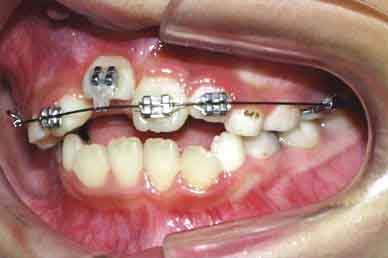

治療開始4ヶ月後